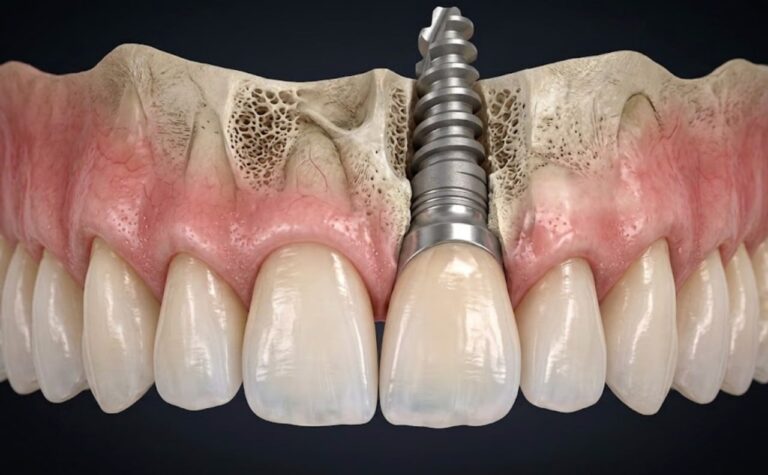

Carico Immediato a Torino: Quando È Indicato

Implantologia

Il carico immediato consente di posizionare una protesi fissa sugli impianti entro 24-48 ore dall’intervento, ma non è una soluzione adatta a…